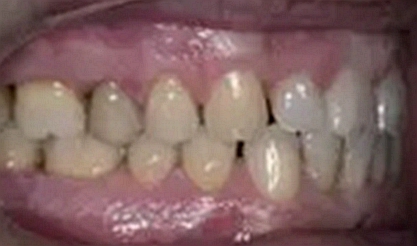

一位尋求改善微笑面容的43歲荷蘭阿爾梅勒男子通過其全科牙醫(yī)的介紹來到一家正畸醫(yī)生的私人診所,以糾正其錯合畸形并在上頜前牙區(qū)域放置6個貼面。他屬于牙形I類錯合畸形,輕度骨性III類,覆合和覆蓋減少以及前牙區(qū)存在間隙(圖1)。

在最初的正畸咨詢期間,拍攝了口內(nèi)和口外照片連同一張全景片(圖2),一張側(cè)位頭影片(圖3)和正畸研究模型的海藻酸鹽印模。